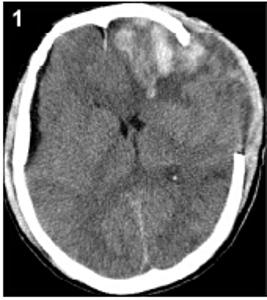

20160503094709

20160503094717

20160503094723

20160503094729